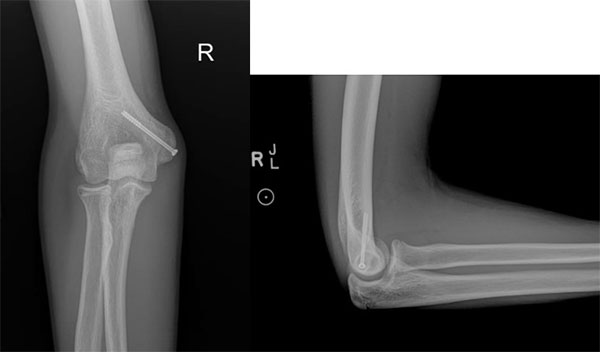

- X-rays demonstrate widening or displacement of the medial epicondyle

- Surgical treatment typically involves open reduction and internal fixation with screw placement across the fractured bone